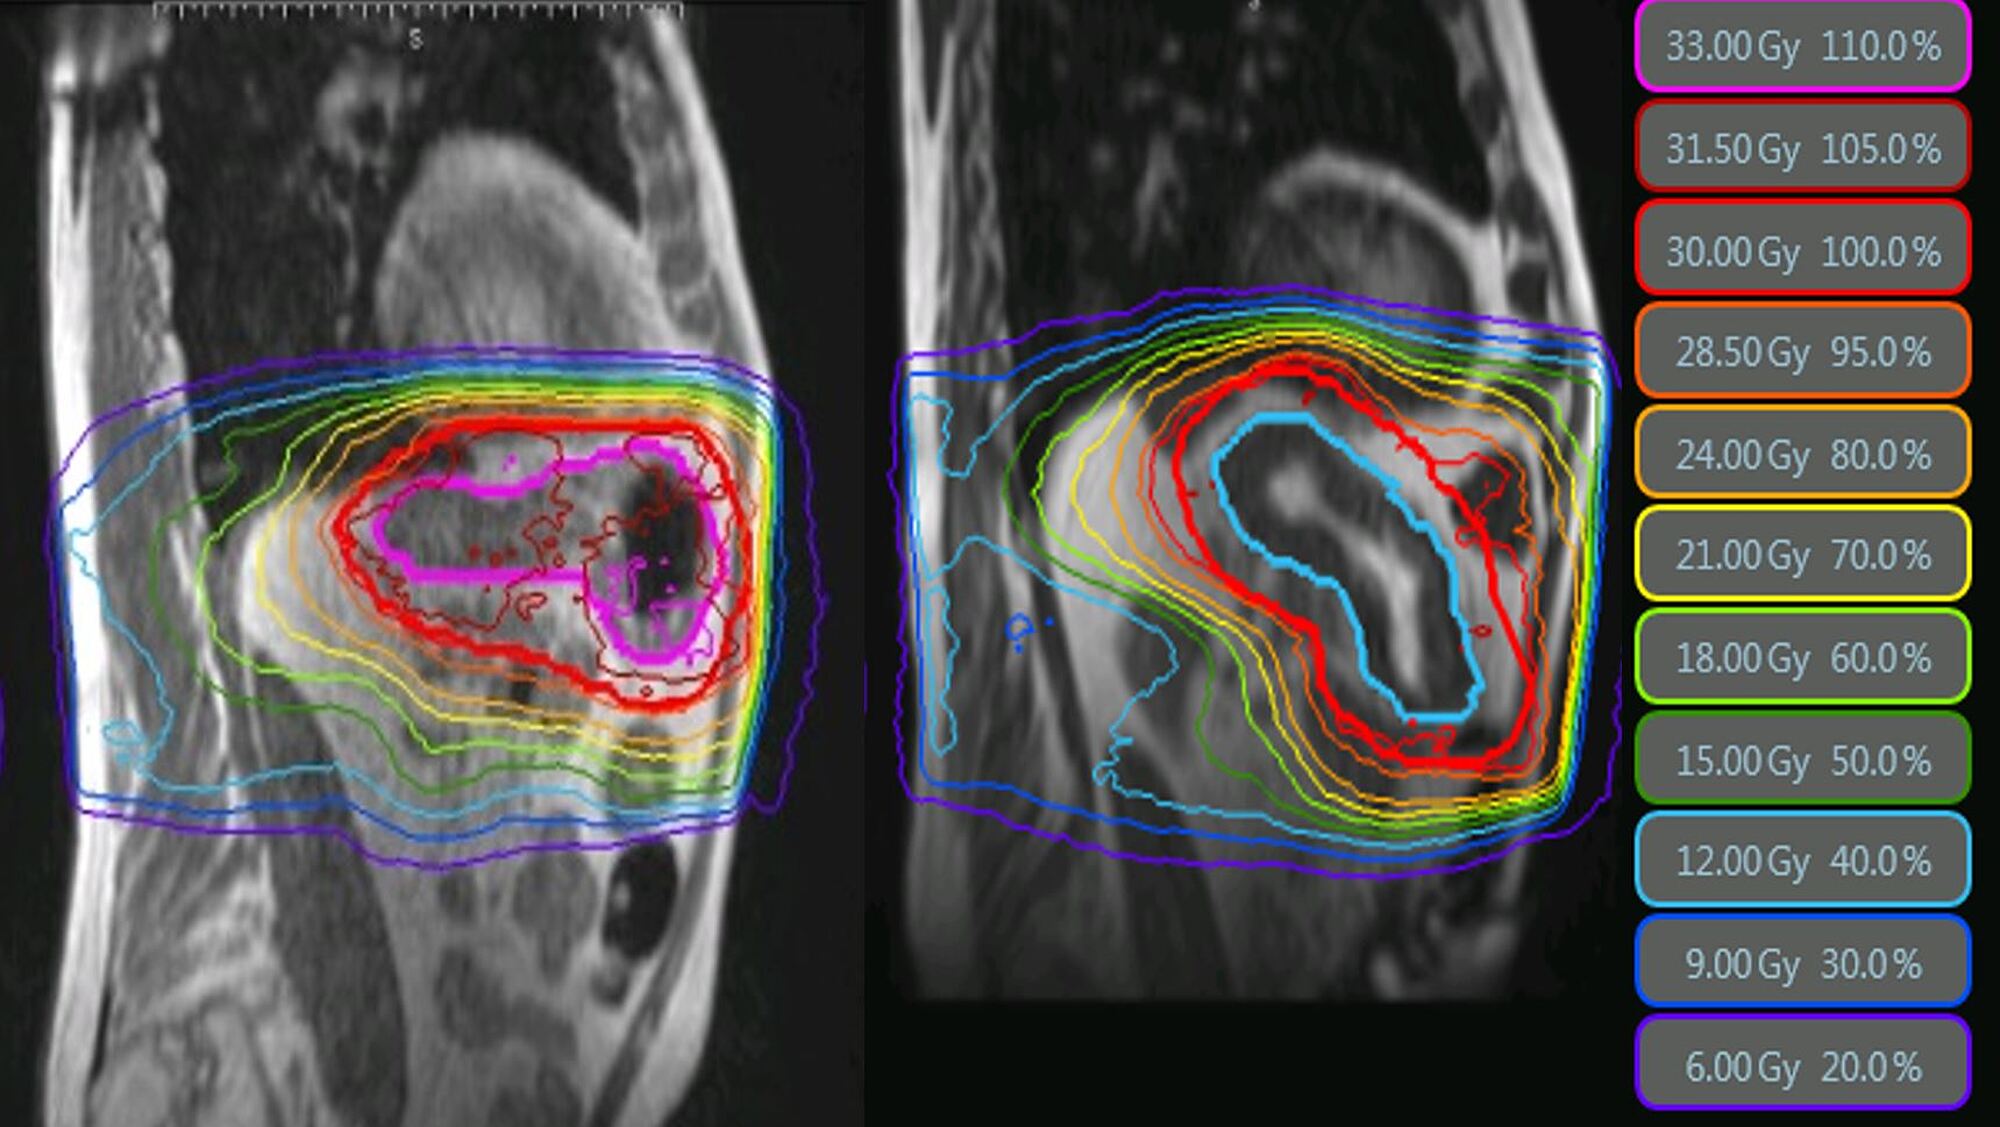

Figure 1 from ResonanceGuided Radiation Therapy to Boost Cervical Cancer When Magnetic Resonance-Guided Radiation Therapy A Review In this special issue of radiation oncology dedicated to the latest advancements in mr guided radiotherapy, a collection of review. Magnetic Resonance-Guided Radiation Therapy A Review.